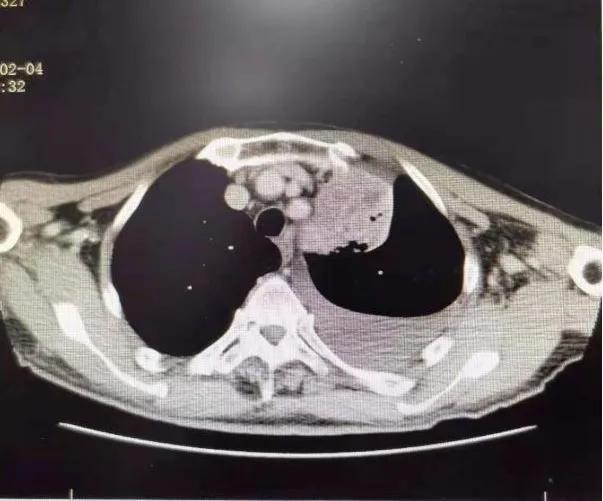

75岁的张爷爷患有慢性阻塞性肺疾病、脑栓塞等多种慢性病,体质较差,PS评分为3分,入院时有咳嗽咯血伴有气短乏力等症状,查胸部CT可见左上肺叶大小约8×4cm大小占位病变,纵隔淋巴结肿大,左侧大量胸腔积液。 气管镜可见左上支气管内新生物阻塞。 病理提示: 鳞状细胞癌。 诊断为: 肺癌(左肺 鳞癌 cT4N2M1a,IVA期)。 确诊后家属考虑患者年老体弱,合并多种疾病,拒绝放化疗,准备放弃治疗。

1个月后张爷爷来院复诊,复查胸部CT提示:左肺上叶肿块缩小到1cm,肺不张明显缓解,胸腔积液减少 。 张爷爷表示近1月来状态明显好转,未再咯血,活动也不像之前那样一动就喘,平时走路吃饭都不影响。入院后PS评分1分,临床疗效评估为PR。 为更好的控制肿瘤,进行了第二次介入治疗。 行支气管动脉及胸廓内动脉造影后显示肿瘤染色明显减少,继续灌注化疗药物后,将肿瘤滋养动脉进行了彻底栓塞。 术后无不适, 顺利完成第二次治疗。